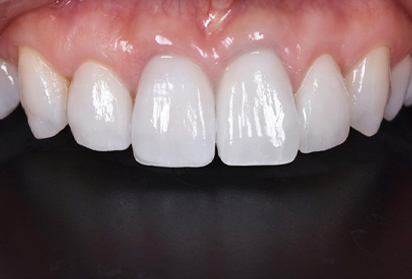

初診時

患者様の主訴は、「前歯の隙間が気になる」

でした。

矯正治療をおすすめしましたが、矯正治療の期間が長いということでセラミック治療を選択することになりました。写真をみるとすきっ歯も気になりますが、以前に詰めたプラスティックも変色して着色しており気になります。

セラミックセット

最終的なジルコニアボンドクラウンをセットしました。すきっ歯がまずなくなりました。また、長かった歯が短くなりましたので本人の希望に沿うことができました。